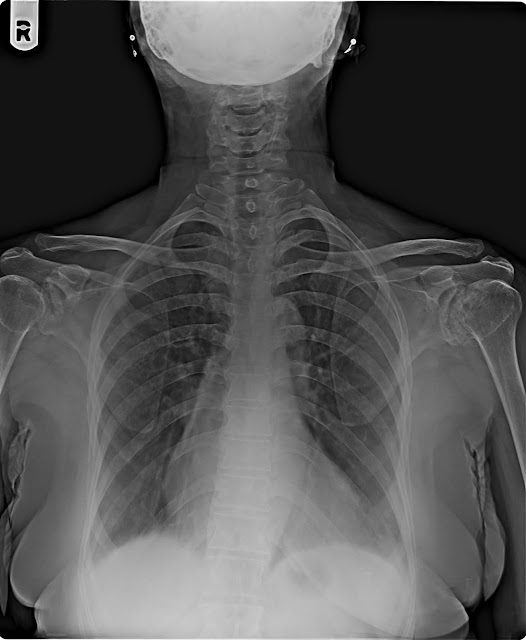

09/06/18 ANANDIBEN PATEL F/65Y CERVICAL-AP/LAT

H/O NECK LT. SHOLDER PAIN LAST ONE MONTH

X-RAY CERVICAL

SPINE AP & LATERAL VIEW

The bone density is normal.

No obvious lytic or sclerotic lesion.

Degenerative changes in form of osteophytes seen in cervical spine.

Evidence of reduction in IV disc space between C3-C4, C4-C5 & C5-C6.

The cervical vertebral bodies and their appendages

(pedicles and spinous process)

are normal.

The intervertebral joints do not show any abnormality.

The cranio vertebral junction is normal.

The spinal alignment

is maintained (with normal lordotic curve and

alignment of the anterior/posterior spinal lines).

Pre and para vertebral soft tissues do not show any

abnormality.

No evidence of bony cervical ribs seen on either side.